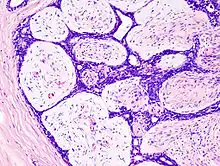

L'adénofibrome (ou fibroadénome) est une tumeur bénigne du sein composée de tissus fibreux et de tissus glandulaires atteignant la glande mammaire. Cette tumeur bénigne est la plus fréquente des tumeurs solides du sein. Elle survient essentiellement chez les jeunes femmes, souvent avant 30 ans, mais peut apparaître à tout âge[1].